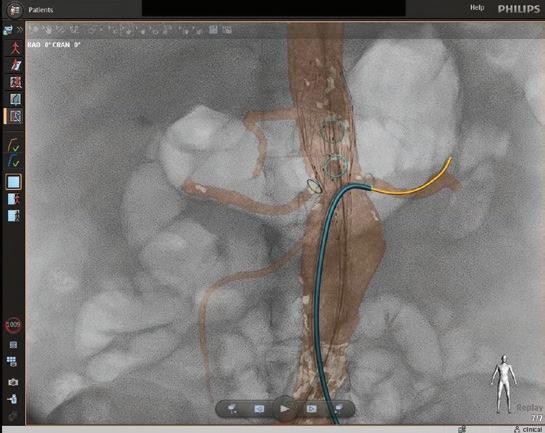

FORS Technology Enhances Visibility and Reduces Radiation Exposure during EVAR

Light refracted through optical fibers generates real-time images of endovascular devices.

Endovascular repairs are done in a hybrid cardiovascular operating room with advanced imaging equipment, a fluoroscopy unit and traditional operating suite. At UMass Memorial Medical Center, the hybrid OR is also equipped with Fiber Optic RealShape (FORS) technology. Surgeons there were the first in the nation to use FORS for a complex endovascular aortic aneurysm repair (EVAR). The technology gives operators better imaging and more flexibility in maneuvering endovascular guidewires and catheters for EVAR, while also reducing dependence on fluoroscopy.

A new technology developed by Philips dramatically improves visibility while also reducing dependence on fluoroscopy. In 2021, UMass Memorial Medical Center vascular surgeons became the first in the nation to use FORS, a technology that generates real-time images of endovascular devices by refracting light through optical fibers. Only two other hospitals in the U.S. and three outside the country are currently using it.

Instead of the ionizing radiation of fluoroscopy, FORS technology uses light refracted through optical fibers to provide 3D tracking of endovascular guidewires, catheters and devices. FORS technology has the potential to reduce a patient’s radiation exposure by as much as 75% during endovascular complex aortic aneurysm repair.

Fiber Optic RealShape technology enhances visibility as the operator moves devices through the arteries. The 3D images enable the team at the Center for Complex Aortic Disease to view progress and movement from any angle.

In addition to reducing the need for fluoroscopy, FORS technology enhances the visibility as the operator moves devices through the arteries. The real-time images produced are three dimensional, so the EVAR team can view progress and movement from any angle. The technology also allows for zooming in and having multiple projections on-screen at once.

“This enables me to always keep the full extent of the guidewire in my field of vision,” Schanzer said. “Then I can advance the FORS catheter over the wire to get it in position. The FORS system shows which portion of the guidewire or catheter is in front of the other, making all endovascular interventions easier and safer.”

The FORS images are displayed on top of, and in alignment with, anatomical patient images created through digital subtraction angiography (DSA) or computed tomography (CT), both of which are black and white. With DSA or CT images alone, it can be difficult to determine the exact placement of the catheter, but with FORS technology, it can be seen in color in the foreground.

“The system is very intuitive and truly represents a new era in device guidance,” Schanzer said, adding that having a color image has an additional benefit. “Until I started using FORS, I hadn’t realized how much operator fatigue there is when you’re only looking at different shades of gray to visualize everything. It’s become very apparent to me that the bright yellow and blue on top of the gray background really decreases that strain, especially when you’re looking at previous stent grafts and wires.”